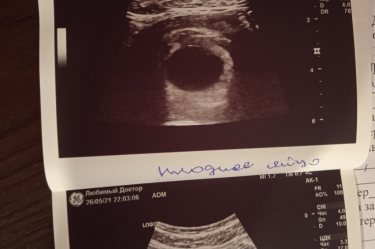

Девочки на 1 фото в ПЯ, в правом верхнем углу что-то видно? Под вопросом анэмбриония. Узи в 6 недель по ПЯ. Пя 17 мм

К сожалению это пустое пя. С таким размером уже эмбрион должен быть. Я через это проходила

При таком размере пя, уже должен быть эмбрион, но у вас что-то пусто… Может ещё всё будет хорошо

Это увеличеное специально. Размер пя всего 17 мм.

Это специально увеличивали. Оно на самом деле маленькое еще 17 мм. И узи поверхностно было

Марина Поверхностно? Тогда это не информативно. Надо вагинально делать. У меня при пя 20 мм, ктр был 2 мм

У меня при ПЯ 21мм еще не было эмбриона на узи. На фото видно что-то, да, у меня похоже было, но покрупнее эта тень была